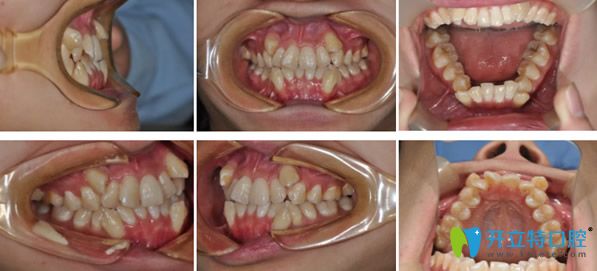

26歲生日剛過(guò),我就來(lái)到了青島拜博口腔,找郁章欣醫(yī)生矯正牙齒了。先看看我的正畸前的照片:牙齒擁擠錯(cuò)亂、虎牙前突。

郁主任面診后,給出的結(jié)論是這樣的:下頜牙列重度擁擠,上下頜雙尖牙偏牙弓頰側(cè)生長(zhǎng),雙側(cè)磨牙II類關(guān)系。典型的安氏II類錯(cuò)頜畸形。